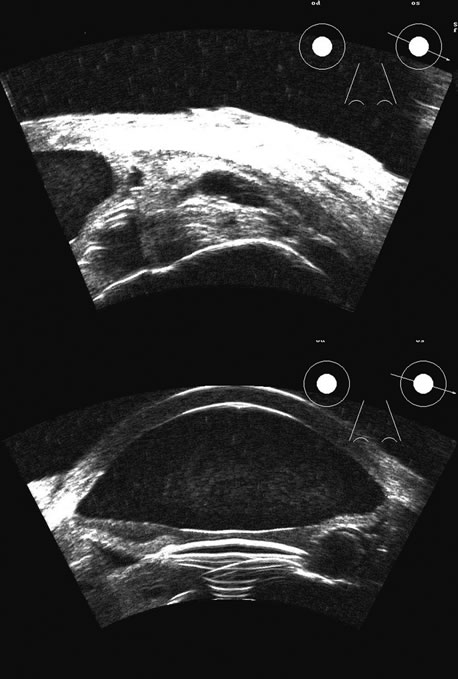

Hypotony is easily diagnosed by direct measurement of intraocular pressure, but the underlying cause is difficult to evaluate.11 High-frequency ultrasound scans can easily reveal separation of the ciliary body and the sclera. This allows different forms of hypotony to be determined—for example: tractional with membrane attached; primary as idiopathic, often inflammatory or hemorrhagic; and dehiscence secondary to iridodialysis or scleral perforation (Fig. 6).

Fig. 6. Hypotony of the eye generally is easily diagnosed by a separation of the ciliary body from the sclera. We have noted several types of such separation, such as tractional, primary (idiopathic), and dehiscence secondary to iridodialysis or scleral perforation, as in filtration procedures. In our series, greater than two clock hours of separation is typical of hypotony. The lower figure shows a concomitant thickening of the retina-choroid complex, also seen in hypotony (arrows). Long-standing hypotony typically has a shortened globe and possible retinal or choroidal separation.